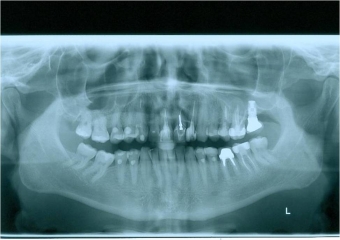

Raio x panorâmico inicial